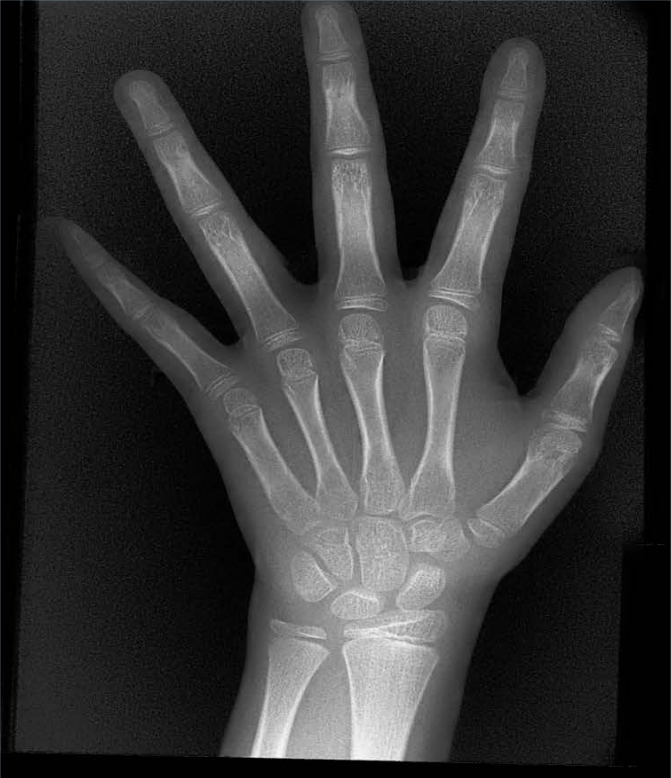

X射線骨齡儀通過(guò)拍攝兒童手腕部(指骨、掌骨、腕骨)的X射線影像,依據(jù)骨骼的形態(tài)、大小、鈣化程度等特征,結(jié)合評(píng)估標(biāo)準(zhǔn)(如《中國(guó)青少年兒童手腕骨成熟度及評(píng)價(jià)方法》,簡(jiǎn)稱《中華-05》標(biāo)準(zhǔn))進(jìn)行骨齡判定。相較于傳統(tǒng)檢測(cè)方式,X射線骨齡儀具有輻射劑量低、影像清晰度高、檢測(cè)效率高的優(yōu)勢(shì),能精準(zhǔn)捕捉骨骼發(fā)育的細(xì)微變化,為骨齡評(píng)估的準(zhǔn)確性提供保障。